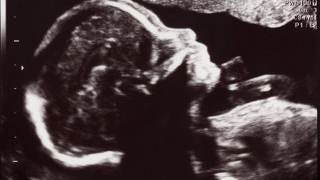

The mistakes came to light after Emily Wheatley (31) was told that she had miscarried following a scan at the University Hospital of Wales (UHW), despite the fact she was carrying a healthy baby.

But she discovered that she was still nine weeks pregnant after later visiting Nevill Hall hospital in Abergavenny for a uterine evacuation – a procedure used after a miscarriage to lower the risk of infection.